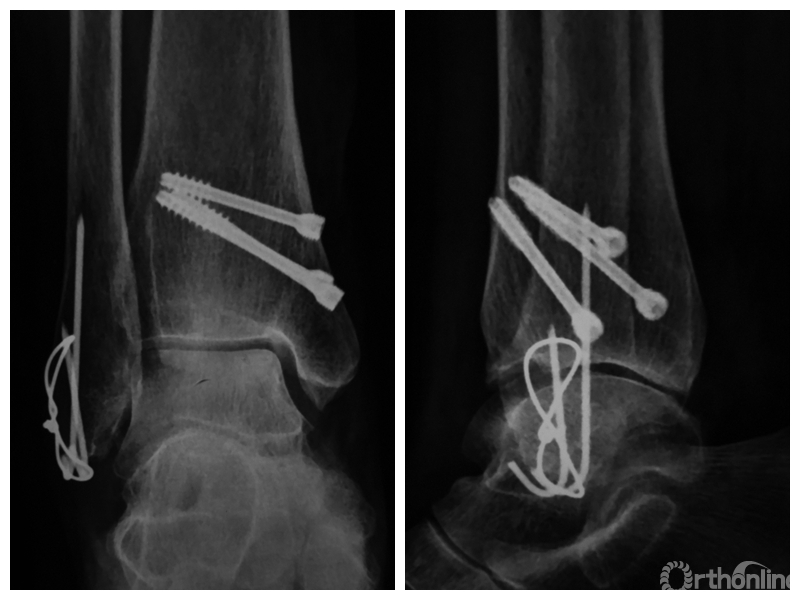

两组患者均获随访,支撑钢板固定组随访时间46~91,平均64.5个月;螺钉固定组随访时间44~86,平均59.5个月。支撑钢板固定组患者术后完全负重时间为(11.5±1.6)周,较螺钉固定组的(12.6±2.3)周显著缩短,比较差异有统计学意义(t=2.05,P=0.04)。X线片复查示,支撑钢板组均获解剖复位,均达愈合;螺钉固定组有20例获解剖复位,2例畸形愈合,1例不愈合,支撑钢板组骨折愈合时间为(11.5±1.6)周,螺钉固定组为(12.0±1.7)周,比较差异无统计学意义(t=1.06,P=0.30)。见图1、2。支撑钢板固定组3例(10%)、螺钉固定组4例(17.4%)发生创伤性关节炎,均采取保守治疗;两组比较差异无统计学意义(P=0.45)。

图1 支撑钢板固定组患者,女,63岁,右侧旋后-内收型II度踝关节骨折 a. 术前正侧位X线片;b. 术前CT;c. 术后2周正侧位X线片;d. 术后2年正侧位X线片

图1c 术后2周正侧位X线片

图1d 术后2年正侧位X线片

图2 螺钉固定组患者,女,37岁,左侧旋后-内收型II度踝关节骨折 a. 术前正侧位X线片;b. 术前CT;c. 术后2周正侧位X线片;d. 术后1年正侧位X线片

图2c 术后2周正侧位X线片

图2d 术后1年正侧位X线片